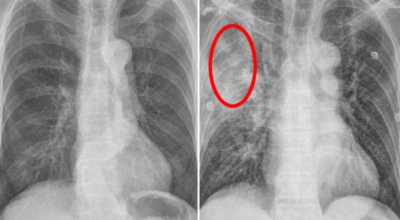

폐암 검사는 X-ray를 통해서 검사하는데 , 크기가 작거나 구석에 위치한 경우 확인이 어려운 경우도 있답니다. 그리고 조직 검사를 통해서 정확한 진단을 하게 되어요. 폐암이 발견되면 종양의 크기나 전이 여부 , 위치에 따라서 수술 여부를 결정하게 됩니다.